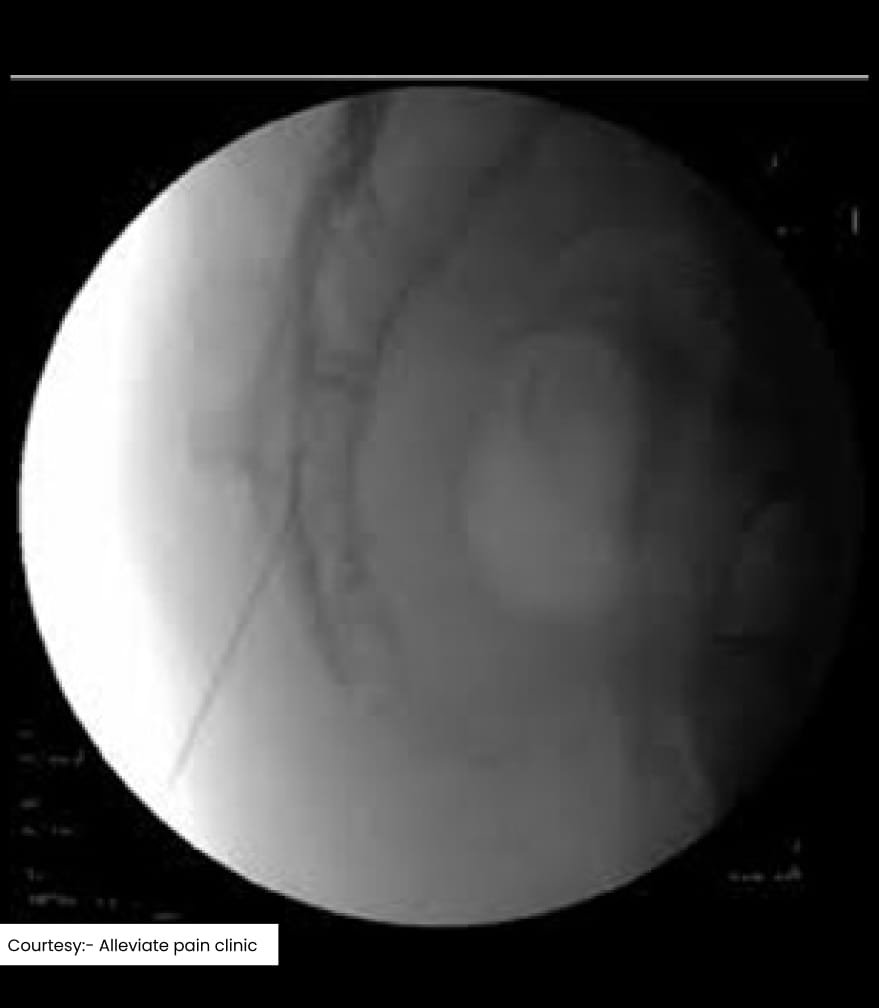

Fluoroscopy guided caudal epidural injection

- Fluoroscopy (X-ray): Provides real-time imaging and is the most commonly used guidance method. A contrast dye is injected to confirm the correct placement of the needle.